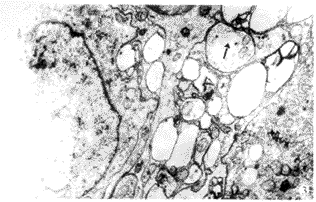

2.2 STC组患者结肠肌间神经丛 与对照组相比,14例STC患者结肠肌间神经丛的超微结构均有明显的病理改变,主要表现在以下两个方面:①神经元及其突起有十分明显的退行性改变,轴突与树突空化呈网格状结构,胶质内出现大小不等的空泡(图1)及脂褐素(图2)等;②轴突末端膨体及突触前区内突触小泡含量明显减少,大部分突触小泡出现空化(图3).

图2 STC组,结肠肌间神经丛神经元胞质内出现大量脂褐素(→) ×12000